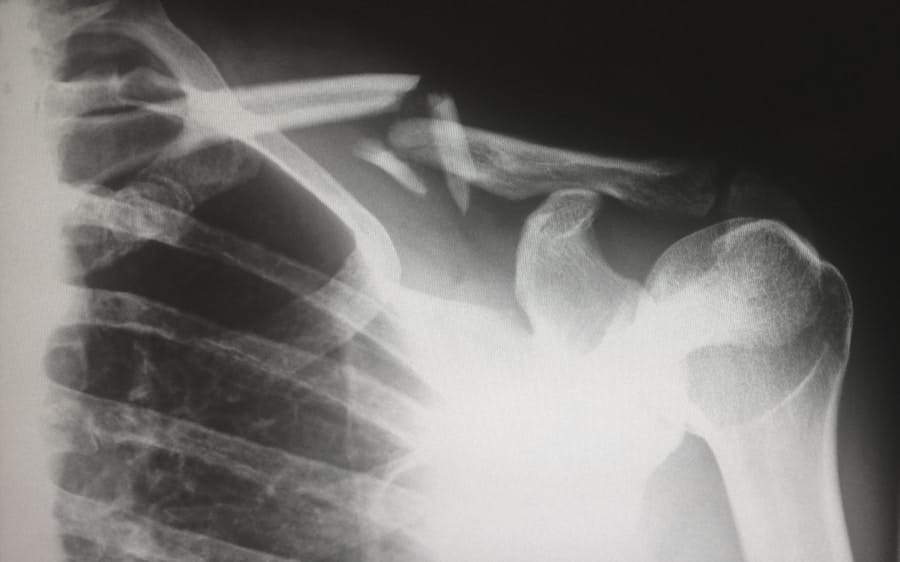

In some cases, these nerve injuries may resolve over time; however, they can also result in long-term functional impairments requiring physical therapy or surgical intervention. In addition to brachial plexus injuries, infants may also experience other complications such as fractures of the clavicle or humerus due to excessive pulling during delivery attempts. In more severe cases, shoulder dystocia can lead to asphyxia if there is a prolonged delay in delivering the baby after the head has emerged.